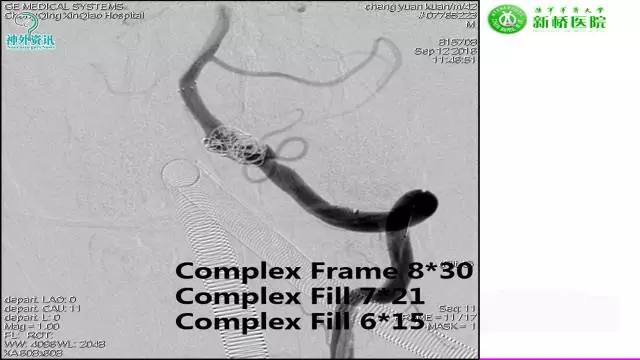

今天为大家分享的是“强生医疗CNV-神经介入专栏”第三十六期,由重庆第三军医大学附属新桥医院神经外科刘俊带来的“Galaxy弹簧圈在不规则动脉瘤中的临床应用”精彩讲课视频及PPT,欢迎观看。文章仅代表作者个人观点,如有不同见解,欢迎同道斧正!